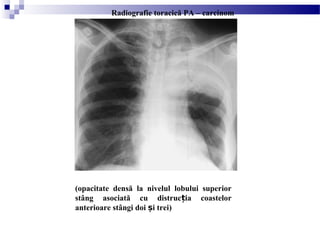

(opacitate densă la nivelul lobului superior

stâng asociată cu distruc ia coastelorț

anterioare stângi doi i treiș )

Radiografie toracică PA – carcinom